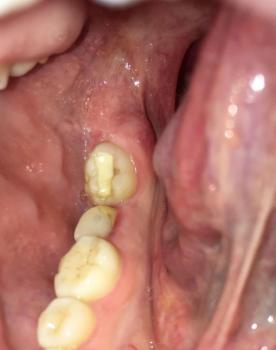

This CBCT image shows the anterior maxillary region with multiple natural teeth. A well-defined radiolucent lesion is visible at the root apex of a previously treated tooth (circled area), indicating a persistent apical infection. Surrounding bone shows early structural changes.